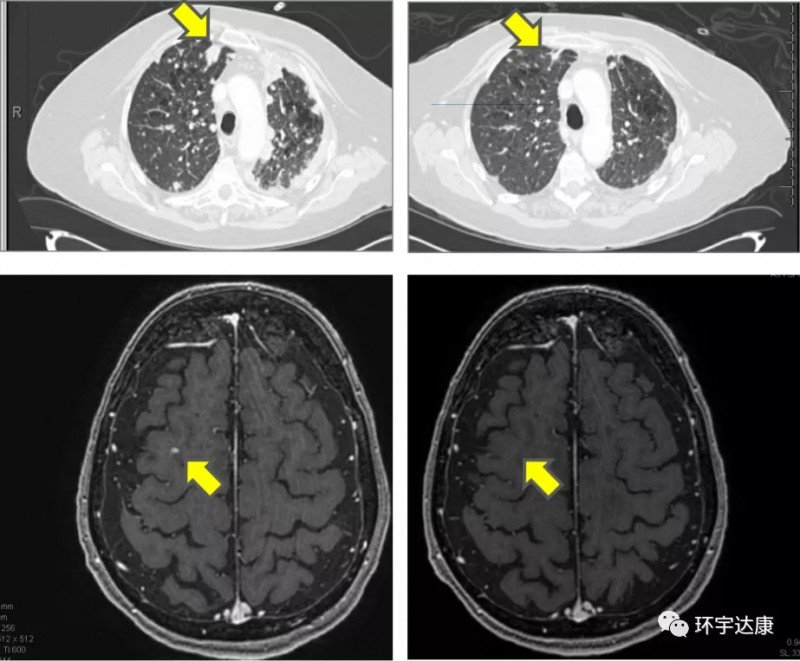

此外,Adagrasib(MRTX849)可以穿透血脑屏障,对于脑转移的患者也有效,会议上报道了一个患者案例:

一位77岁的女性KRASG12C突变非小细胞肺癌患者,既往接受了多种方案的放化疗,PD-1治疗,仍然无法阻止病情进展,出现肝脏和脑部的多发转移,临床上已经没有更好的治疗方案,在接受试验性药物Adagrasib(MRTX849)治疗后7个周期后,肺部病灶缩小67%,脑部病灶消退了!目前仍在接受治疗。

这个数据意义非比寻常,将给KRASG12C突变非小细胞肺癌患者新的治疗机会。